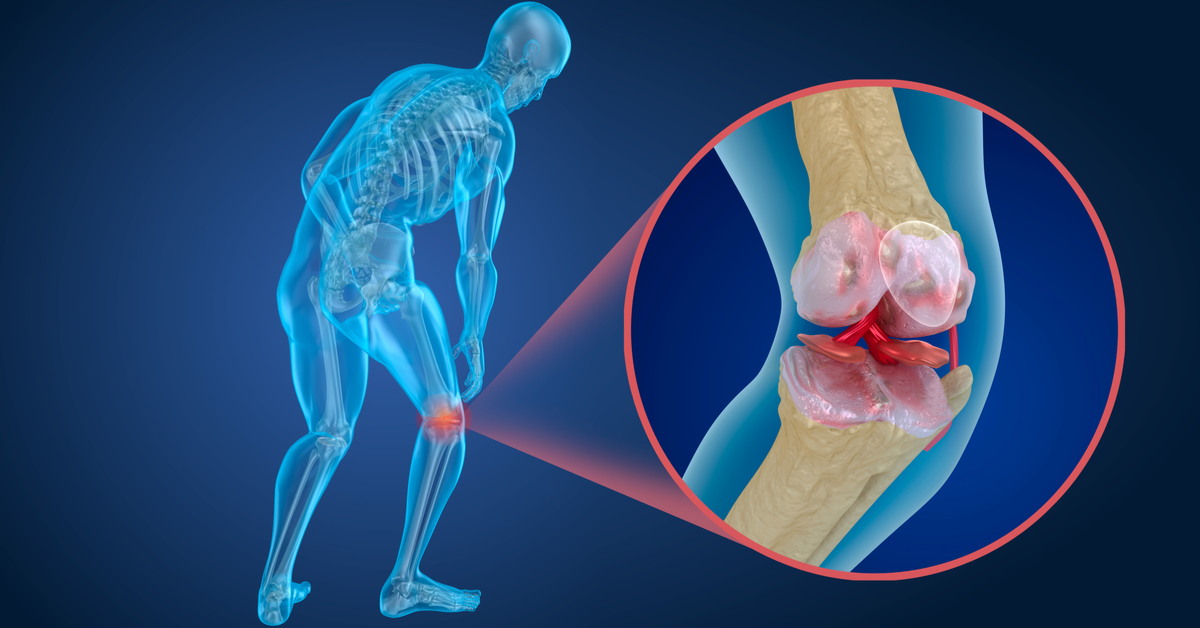

- Rheumatoid Arthritis: Rheumatoid arthritis is a common rheumatic disease that can cause severe joint pain, including in the shoulder joint. This disease damages joint tissues, leading to pain, swelling, and stiffness.

Spinal Disorders: These disorders include arthritis, nerve compression, herniated discs, and other conditions that affect the spine. Neck pain resulting from these disorders may be accompanied by shoulder or back pain. Treatment depends on the type and severity of the disorder and may include physical therapy and medication in some cases.

Arthritis and Cartilage Inflammation: The joints in the shoulder and the cartilage can be affected when the cartilage begins to break down, causing inflammation and pain. The reason for shoulder pain when sleeping on it may be joint or cartilage inflammation.